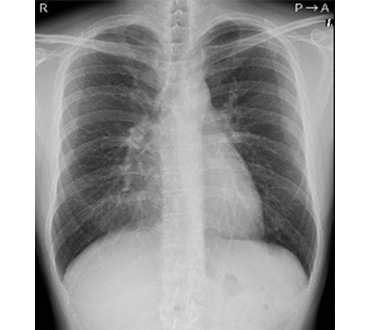

一般撮影室

主にレントゲン写真と呼ばれていてX線を利用し、胸部、腹部、骨などの撮影をします。人体にX線をあて透過したX線をコンピュータで処理し画像にします。迅速に画像を提供できることから、日常の診断に最も多く利用されている検査です。